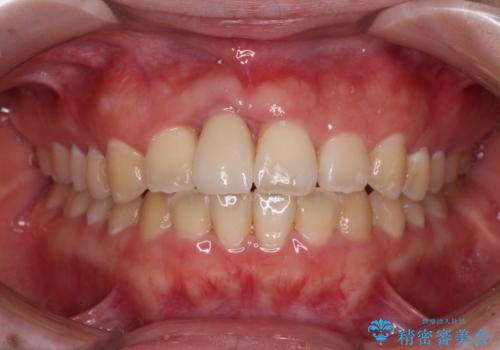

- 中学生の頃にぶつけた前歯に不格好なクラウンが装着されており、出っ歯な印象になっていることを気にして来院された患者様です。

ぶつけてしまった歯は保存が困難な状況であったので抜歯をし、ワイヤー矯正により歯列を整えつつ前歯の突出感を解消することとしました。

矯正治療後にはインプラント補綴治療を行うこととしました。

前歯の補綴治療はインプラントかブリッジかで悩んでいました。

周りの歯にむし歯がないため、インプラントがお勧めとなりますが、事故による骨欠損が大きく、歯肉ラインを整えるのが困難という問題がありました。